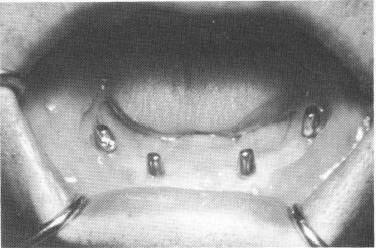

Fig. 12-32. Healing of the soft tissues covering the implant usually is completed 3 to 6 weeks after its insertion.

After about 3 to 6 weeks, the implant should have completely set and the surrounding tissues should be sufficiently healed to take the final "pick-up" impression for the final implant prosthesis (Fig. 12-32) . The superstructure framework is first placed over the four implant abutments (Fig. 12-33), and an accurate wax or stone occlusal record of centric relation is taken and the vertical dimension established (Fig. 12-34) . The superstructure is then picked up with one of the elastic impression materials (Fig. 12-35) or with one of the alginate materials (Fig. 12-36). All the soft tissue underneath the superstructure should be included in this impression. Instead of processing the denture, a wax-up of acrylic teeth fitted to the metallic superstructure should be tried during the next visit so that the bite, articulation, vertical dimension, and balancing of the case can be corrected (Fig. 12-37). Finally, the com-

Fig. 12-33. The superstructure framework is placed over the protruding implant posts.